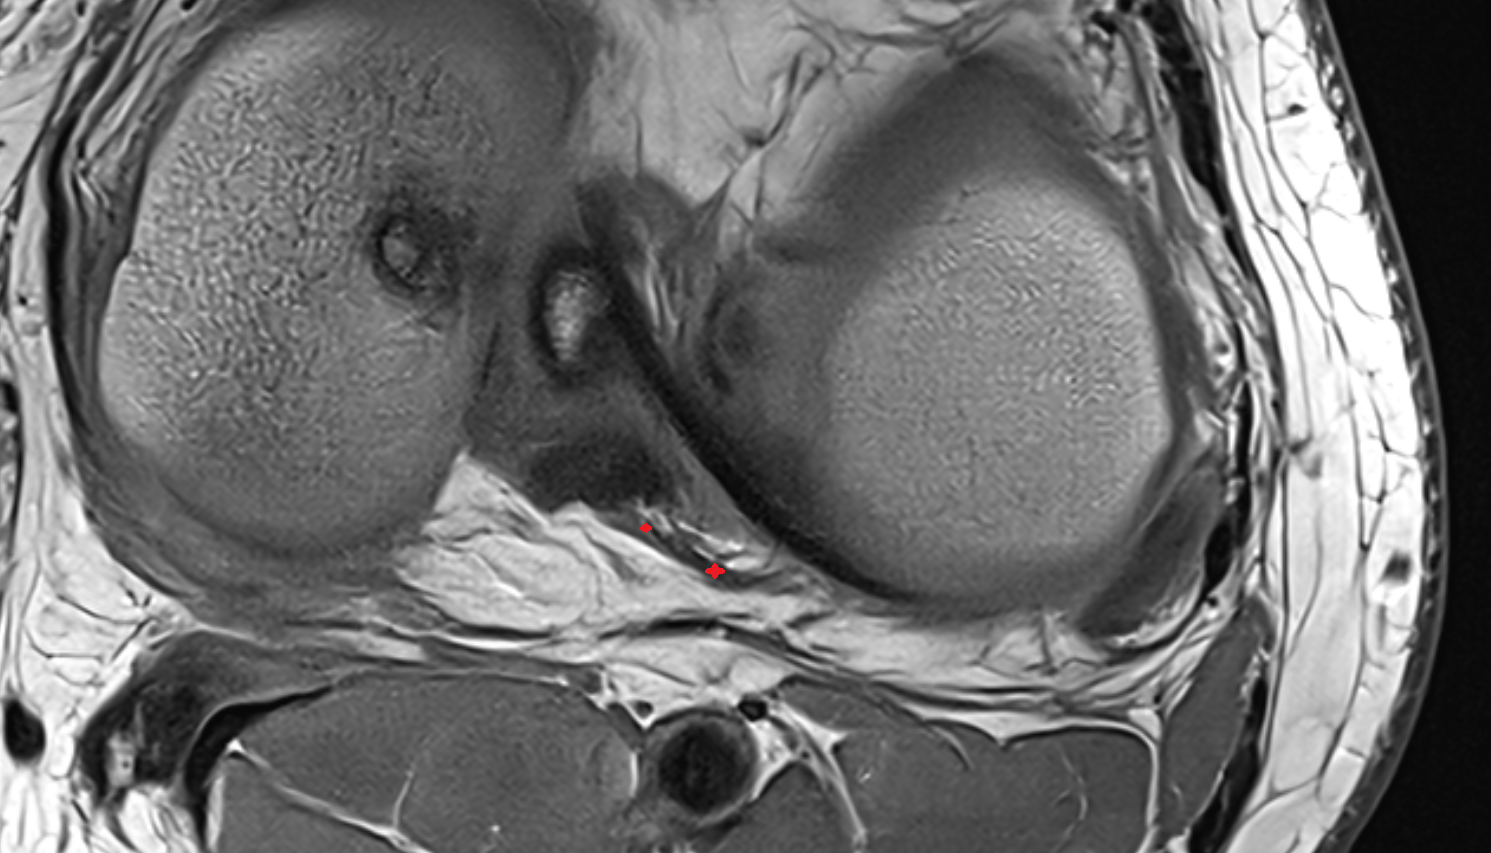

- Medial meniscus

- Lateral meniscus

- Anterior horn of medial meniscus

- Posterior horn of medial meniscus

- Body of medial meniscus

- Anterior root of medial meniscus

- Posterior root of medial meniscus

- Anterior horn of lateral meniscus

- Posterior horn of lateral meniscus

- Body of lateral meniscus

- Anterior root of lateral meniscus

- Posterior root of lateral meniscus